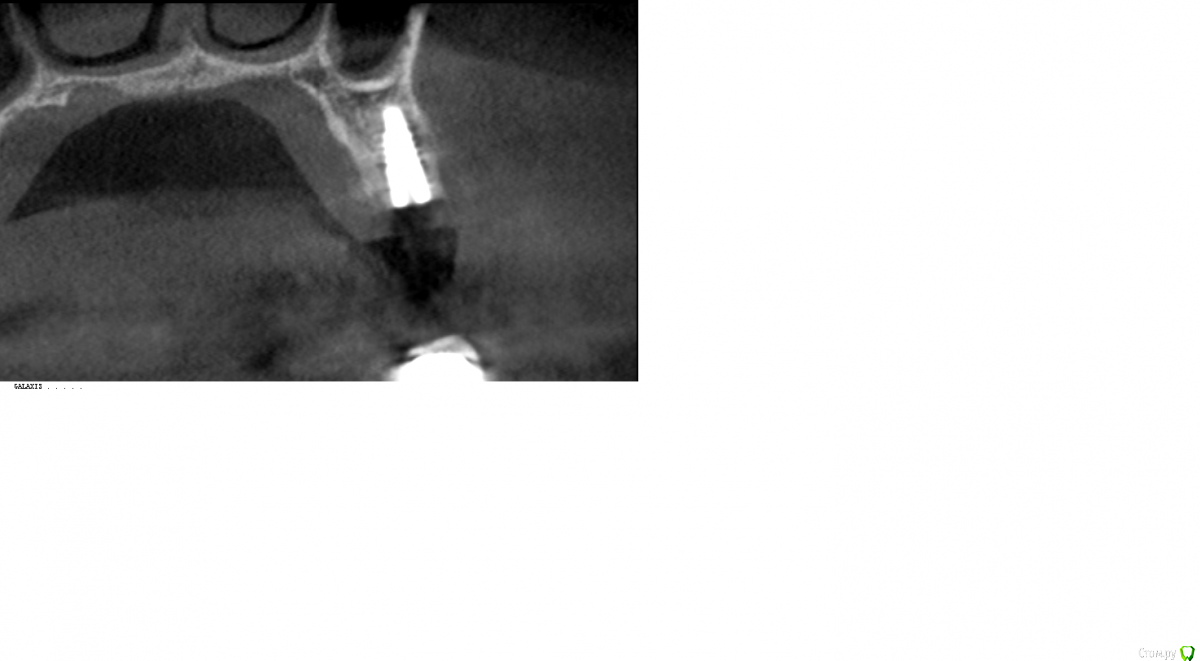

Robinbobin Опубликовано 9 февраля, 2016 Поделиться Опубликовано 9 февраля, 2016 Представляю вашему суду работу с хирургическим шаблоном были установлены имплантаты ИРИС в области 2.5 зуба 3D заполнение и немедленная нагрузка.коронки были изготовлены прямым методом 13 Ссылка на комментарий

АнтонТЛТ Опубликовано 9 февраля, 2016 Поделиться Опубликовано 9 февраля, 2016 А на самом деле, получается, что шаблон и не нужен был? Я про мезиальный имплантПо шаблону он весь в кости, если отталкиваться от протетики, нужно было бы костную пластику делать Ссылка на комментарий

КДБ Опубликовано 10 февраля, 2016 Поделиться Опубликовано 10 февраля, 2016 возможно после формирования ложа по шаблону оператор просто нЕсколько изменил путь введения медиального имплантата,вот и результат.Но расстраиваться не стоит,у нас бывают и более интересные случаи))) Ссылка на комментарий